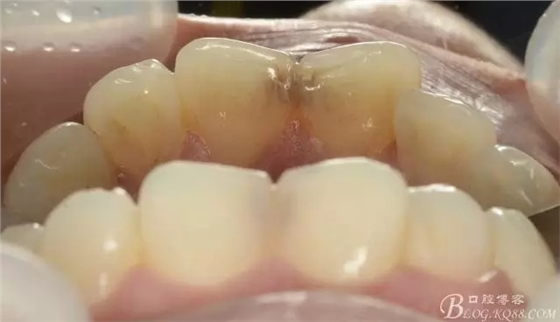

舌側(cè)觀

口腔檢查:11與21之間可見齲壞,探診未見明顯疼痛與缺損,牙齦未見明顯紅腫,無叩痛,冷熱刺激無不適,未見松動(dòng)。兩近中切角收少許,舌側(cè)中1/3課件齲壞,探診可有粗糙感,質(zhì)地硬而黑,牙線經(jīng)過鄰面未見異常,切端可見少許磨耗,咬合張口可,關(guān)節(jié)無壓痛彈響,淺覆合淺覆蓋。